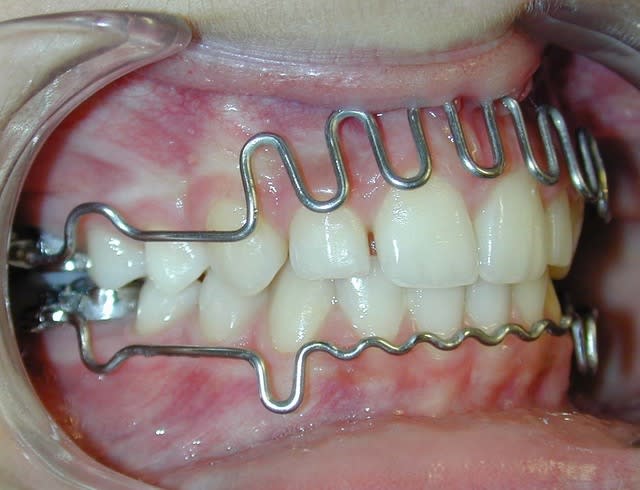

cas 2;Lea

BHG 9mois PUIS eln +2 LBs 15mois

l'occlusion;

NB: Dans les 2 cas , pas de version des inc infs!